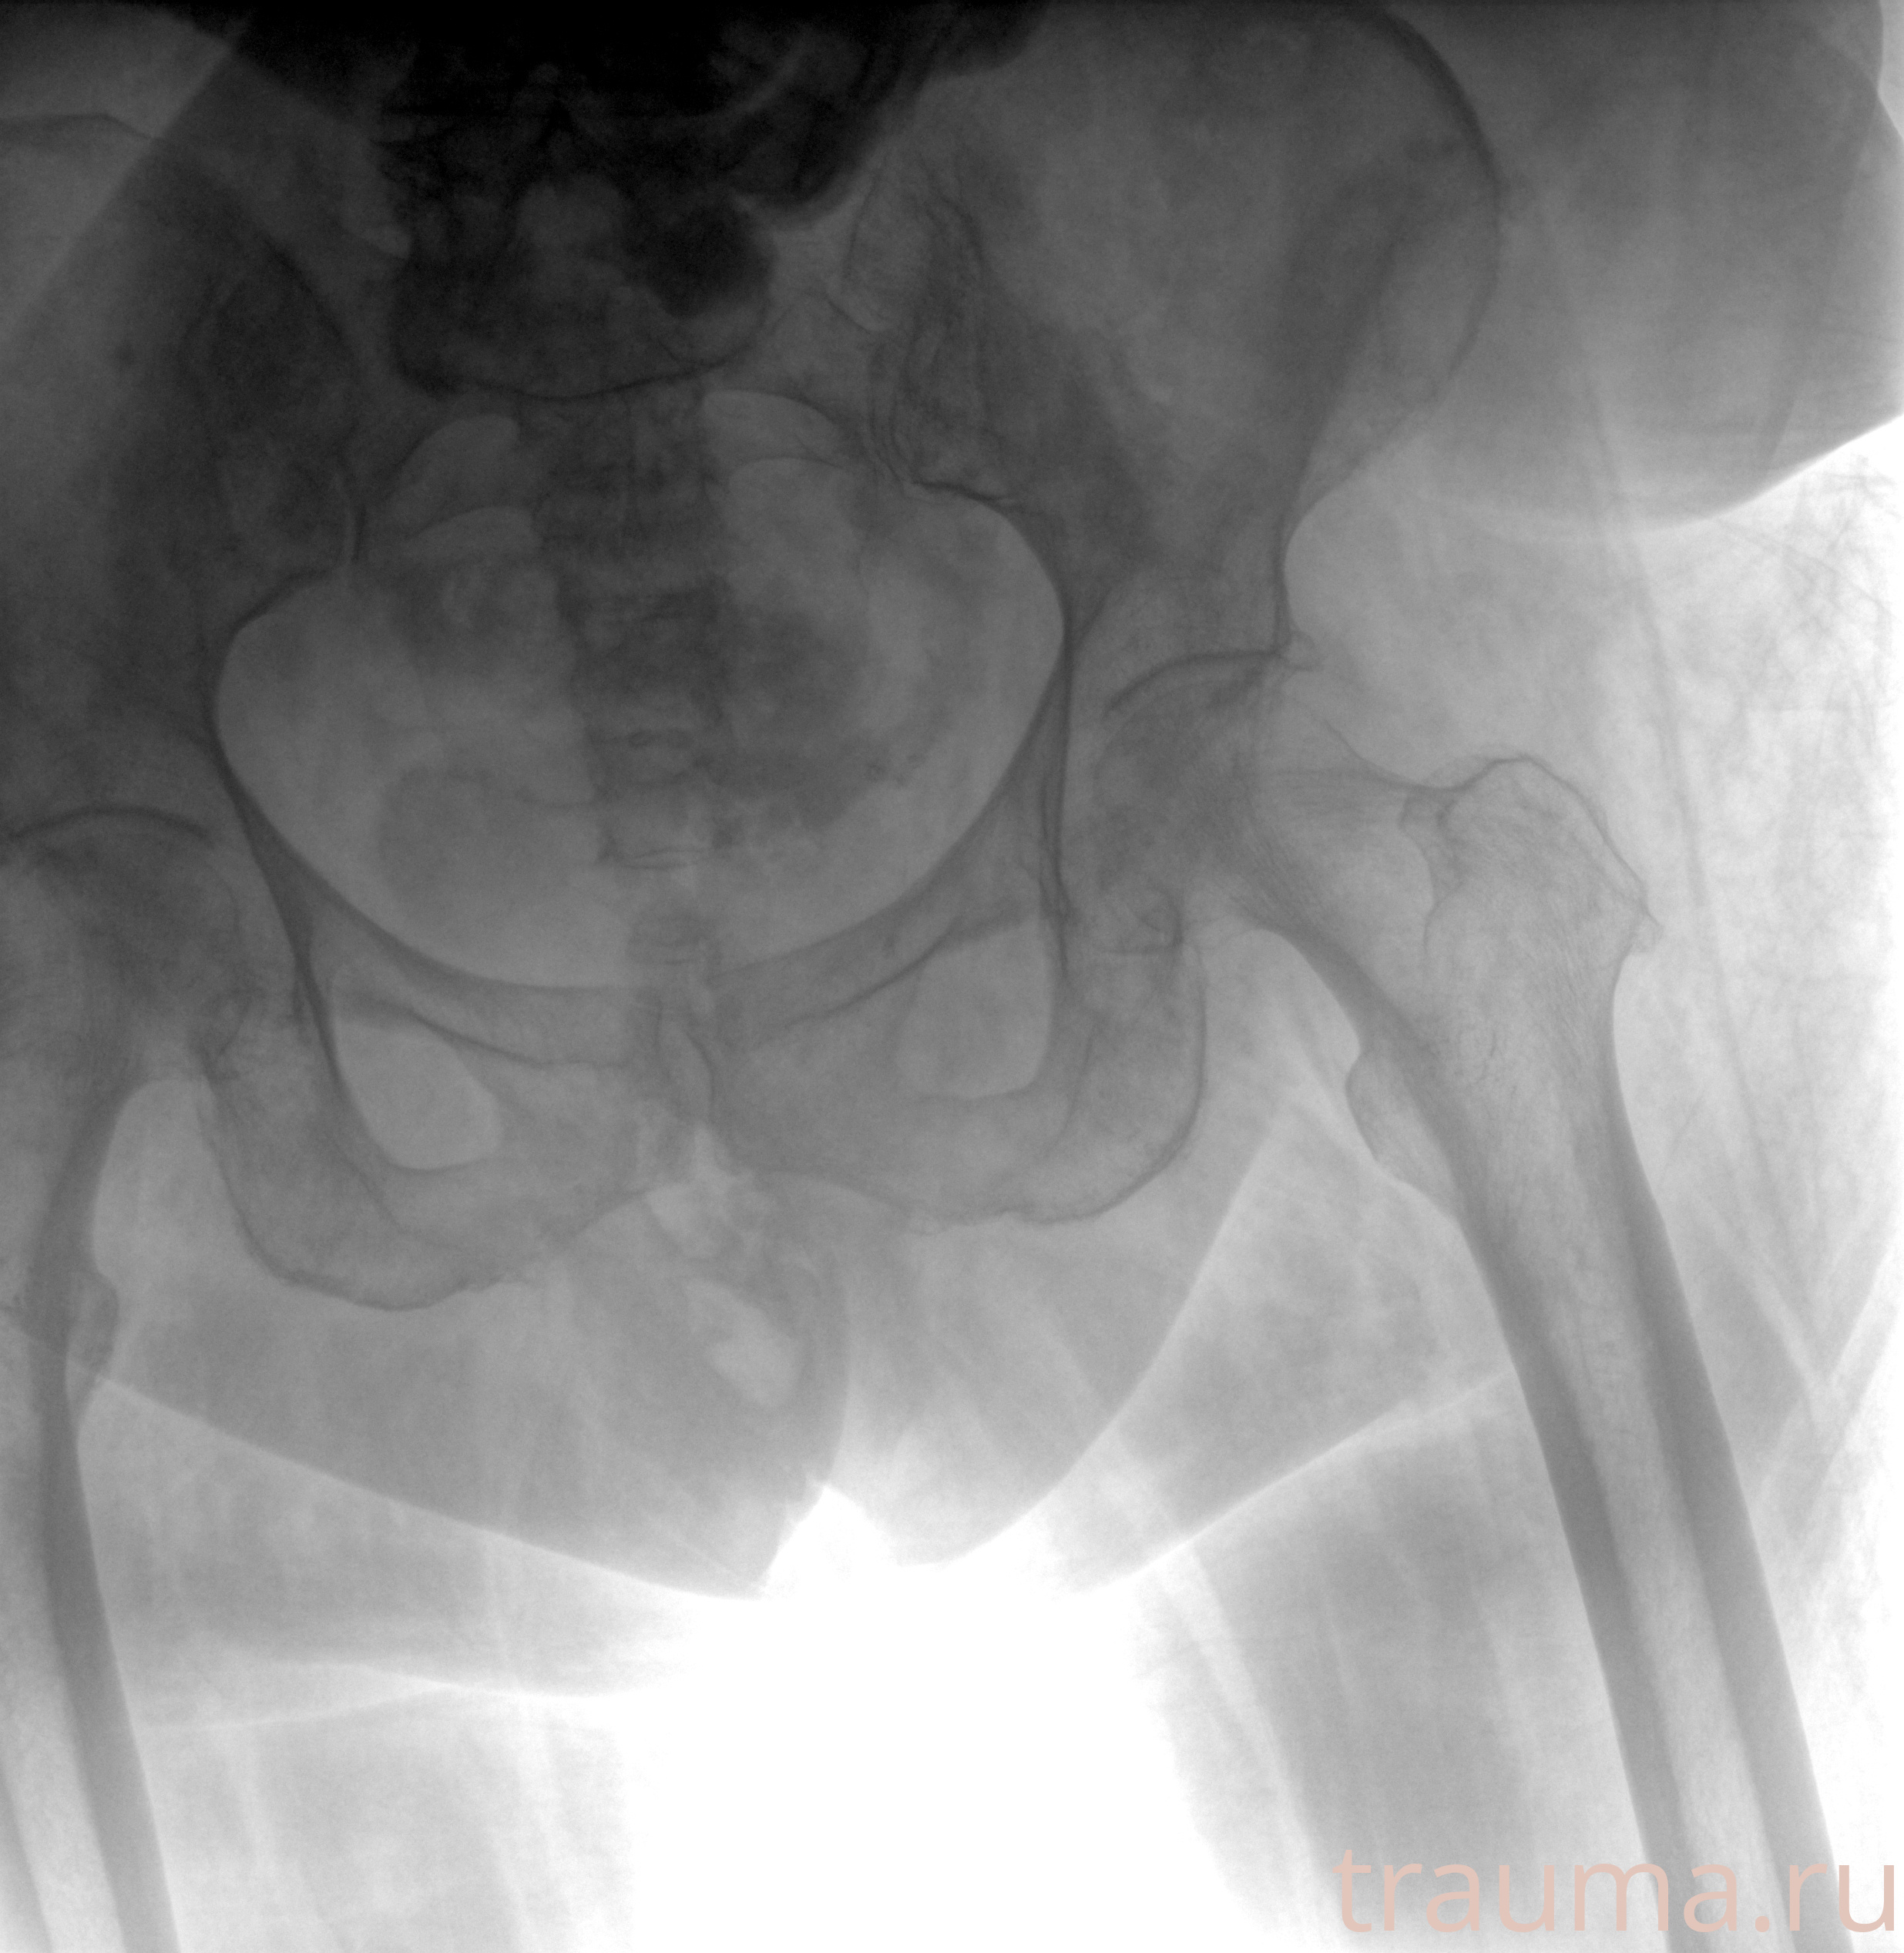

Рентген на дому: по вашему адресу приезжает врач-рентгенолог, травматолог-ортопед с мобильным рентгеновским аппаратом, проводит диагностику травмы или заболевания, делает необходимые рентгенограммы, дает рекомендации по дальнейшему лечению. Получить качественные снимки в домашних условиях возможно благодаря уникальной методике, разработанной МосРентген Центром для института  Склифосовского

при переломе шейки бедра и пневмонии от компании МосРентген Центр - партнера Института имени Склифосовского